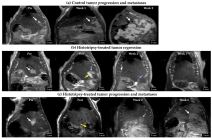

Uništavanjem od 50 do 75 odsto tumora, imuni sistem pacova je uspeo da se izbori sa ostatkom, a rezultati pokazuju uspešan oporavak kod više od 80% životinja. Vodeći profesor istraživanja Žen Ksu je izjavio da čak iako tretman ne uspe da zahvati ceo tumor, oni mogu uspešno da izazovu proces regresije i smanje rizik od budućih metastaza.

Rezultati pokazuju i da tretman podstiče reakciju imunog sistema koji izaziva regresiju delova koji nisu targetirani u procesu, čime se sprečava dalje širenje kancerogenih ćelija.

Problem sa kanceroznim ćelijama je što se u većini slučajeva tumor ne može ciljati direktno zbog različitih stvari: lokacije, mase ili faze razvoja. Kako bi se ispitali efekti parcijalnog uništavanja tumora ultrazvukom, u poslednjoj sprovedenoj studiji je ciljan samo deo svake mase, ostavljajući deo tumora, kako bi se ispitala efektivnost u uslovima koji nisu optimalni.